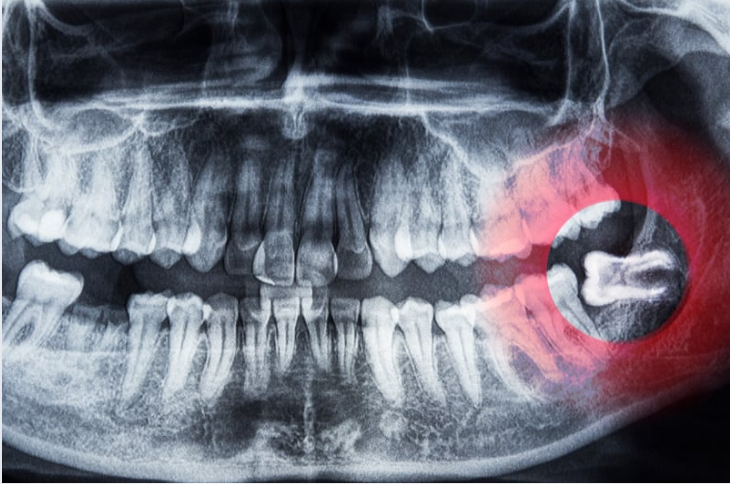

Every extraction begins with a thorough evaluation. Digital X-rays and a careful review of medical history let us assess root anatomy, bone support, and any risk factors for healing. Local anesthesia is the foundation of comfort for most procedures; for patients who experience anxiety or require deeper relaxation, our clinicians can discuss additional sedation options to ensure a comfortable experience.

Skilled clinicians tailor the technique to the tooth’s condition. A straightforward, fully erupted tooth is often removed with controlled forceps after loosening the periodontal ligament. Teeth that are broken at the gumline or fully or partially impacted typically require a surgical approach that may include minor incisions and suturing to access and remove the root segments with minimal disruption to surrounding tissues.

There are several clinical situations in which extraction is the best choice. Extensive decay that leaves the tooth non-restorable, a large abscess that threatens adjacent teeth or bone, and severe root or crown fractures are common triggers. Impacted wisdom teeth that cause recurrent pain, infection, or crowding are another frequent reason for extraction.